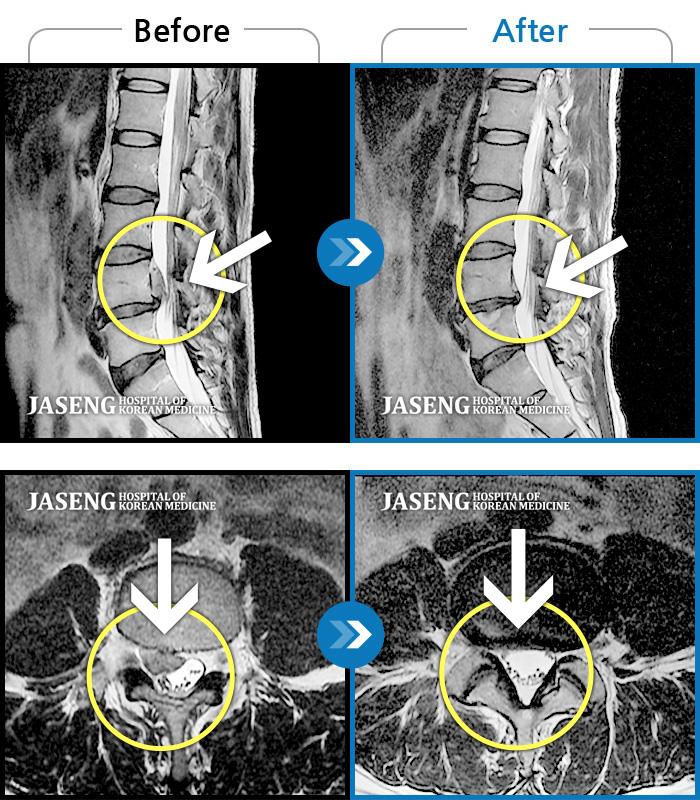

Before

After

환자에게 사전 동의를 받아 동일 조건에서 촬영되었습니다.

개인에 따라 치료 후 부작용이 발생할 수 있으니 의료진과 상담 후 치료를 진행하시기 바랍니다.

양측 허리 통증, 좌측 하지 후면 통증 및 저림 증상

우측 허벅지부터 종아리까지 저리고 통증, 서있을때 증상 심화